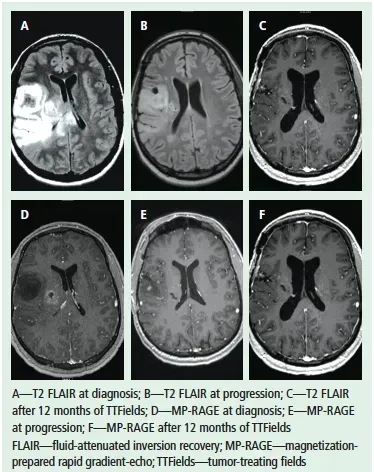

神经肿瘤科团队对多种方案(含临床试验选项)评估后,患者最终选择肿瘤电场疗法(TTFields)。令人振奋的是,经过7个月治疗,患者恢复状况良好。下图展示了该患者在电场疗法治疗前后的MRI对比。

▲图源“MDPI”,版权归原作者所有,如无意中侵犯了知识产权,请联系我们删除